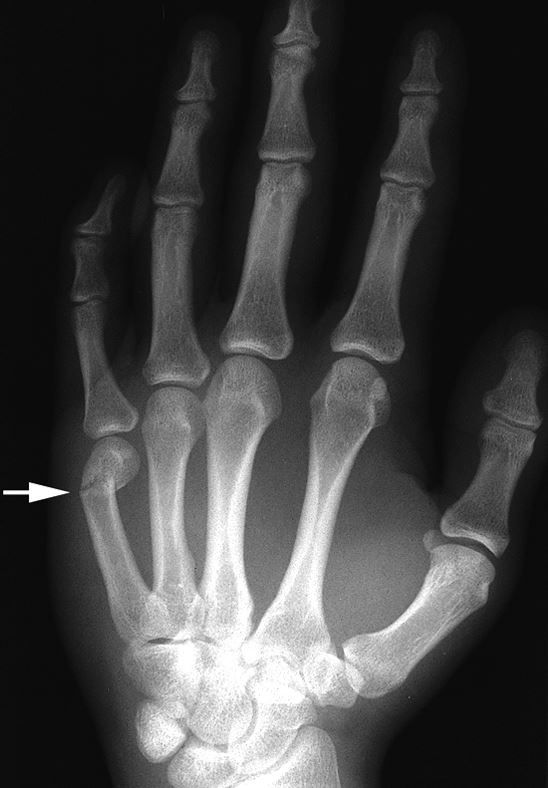

Avulsion fracture - Definition

A ligament or tendon pulls away from its attachment on the bone, and a fragment of bone breaks off with it

Avulsion fracture - Cause

A muscle contraction or stretch that is stronger than the force that holds the tendon or ligament to the bone